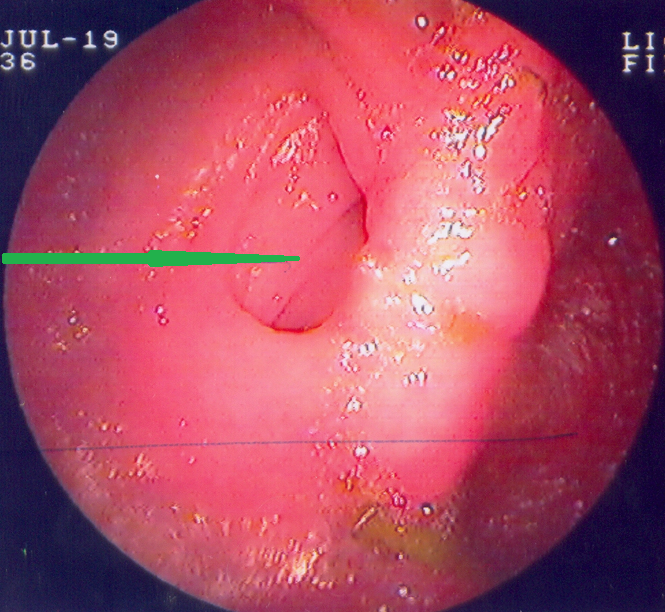

Πράσινο βέλος – εστιακή εξέλκωση κολικού βλεννογόνου. Κίτρινο βέλος – οίδημα και λεμφοκυτταρική διήθηση υποβλεννογόνιου χιτώνα (Ευγενική παραχώρηση Dr. V. Penopoulos)